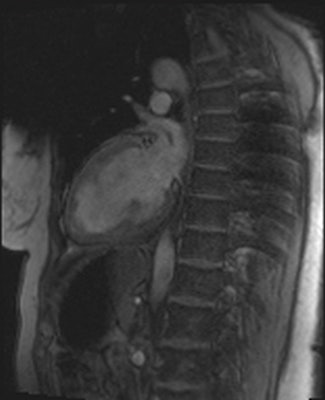

The mean age of the patients was 67 ± 14 years, and 42% (27/64) were women. Altogether 21 (31%) of the examinations were scans of the thorax area, and 20 (29%), 17 (25%), and 16 (24%) of the examinations were MRI scans of spine, head, and heart respectively. The remainder was scans of the pelvis, liver, vagina, rectum, wrist, lung, carotid artery, and soft tissue of the neck, pancreas, and knee.

One of the authors (Sami Pakarinen, HUS Department of Cardiology, Helsinki University Central Hospital) declared a conflict of interest, having been a consultant for St. Jude Medical, Medtronic, Boston Scientific and Biotronik.